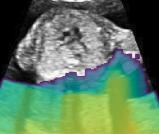

Fig. 6 compares the shadow confidence maps of the state-of-the-art methods and the proposed methods. RW and have the same parameters as used for Table I. The shadow confidence maps of the baseline, the proposed method and the proposedAG method are generated directly from input shadow images by confidence estimation networks. Overall, the proposed method and the proposedAG method achieve more visually reasonable shadow confidence estimation than the baseline and the state-of-the-art on different anatomical structures shown in Fig. 6. The proposed method and the proposedAG method are able to highlight multiple shadow regions while the RW algorithm shows limitations for most cases, especially for disjoint shadow regions.

Row I in Fig. 6 shows a fetal brain image from . The confidence estimation of shadow regions from the baseline, the proposed method and the proposedAG method are similarly accurate since we use fetal brain images to train the confidence estimation networks in these three methods. These outperform [16] and [22]. Rows (II-IV) in Fig. 6 show shadow confidence maps of non-brain anatomy from , including lips, abdominal and cardiac. The baseline failed on unseen data during inference. However, the proposed methods are able to generate accurate shadow confidence maps because of the generalized shadow features obtained by the shadow-seg module. Furthermore, the “Lips” example shows that our method is capable of detecting weaker shadow regions that have not been annotated in manual segmentation. This indicates that the confidence estimation network has learned general properties of shadow regions.